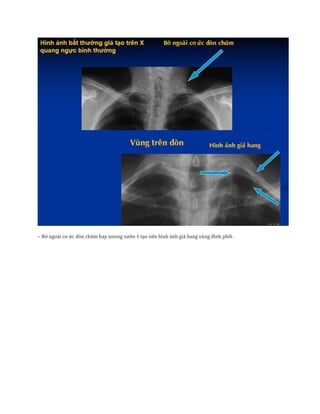

– Bờ ngoài cơ ức đòn chũm hay xương sườn 1 tạo nên hình ảnh giả hang vùng đỉnh phổi .

– Bờ ngoàicơ ức đòn chũm hay xương sườn 1 tạo nên hình ảnh giả hang vùng đỉnh phổi .